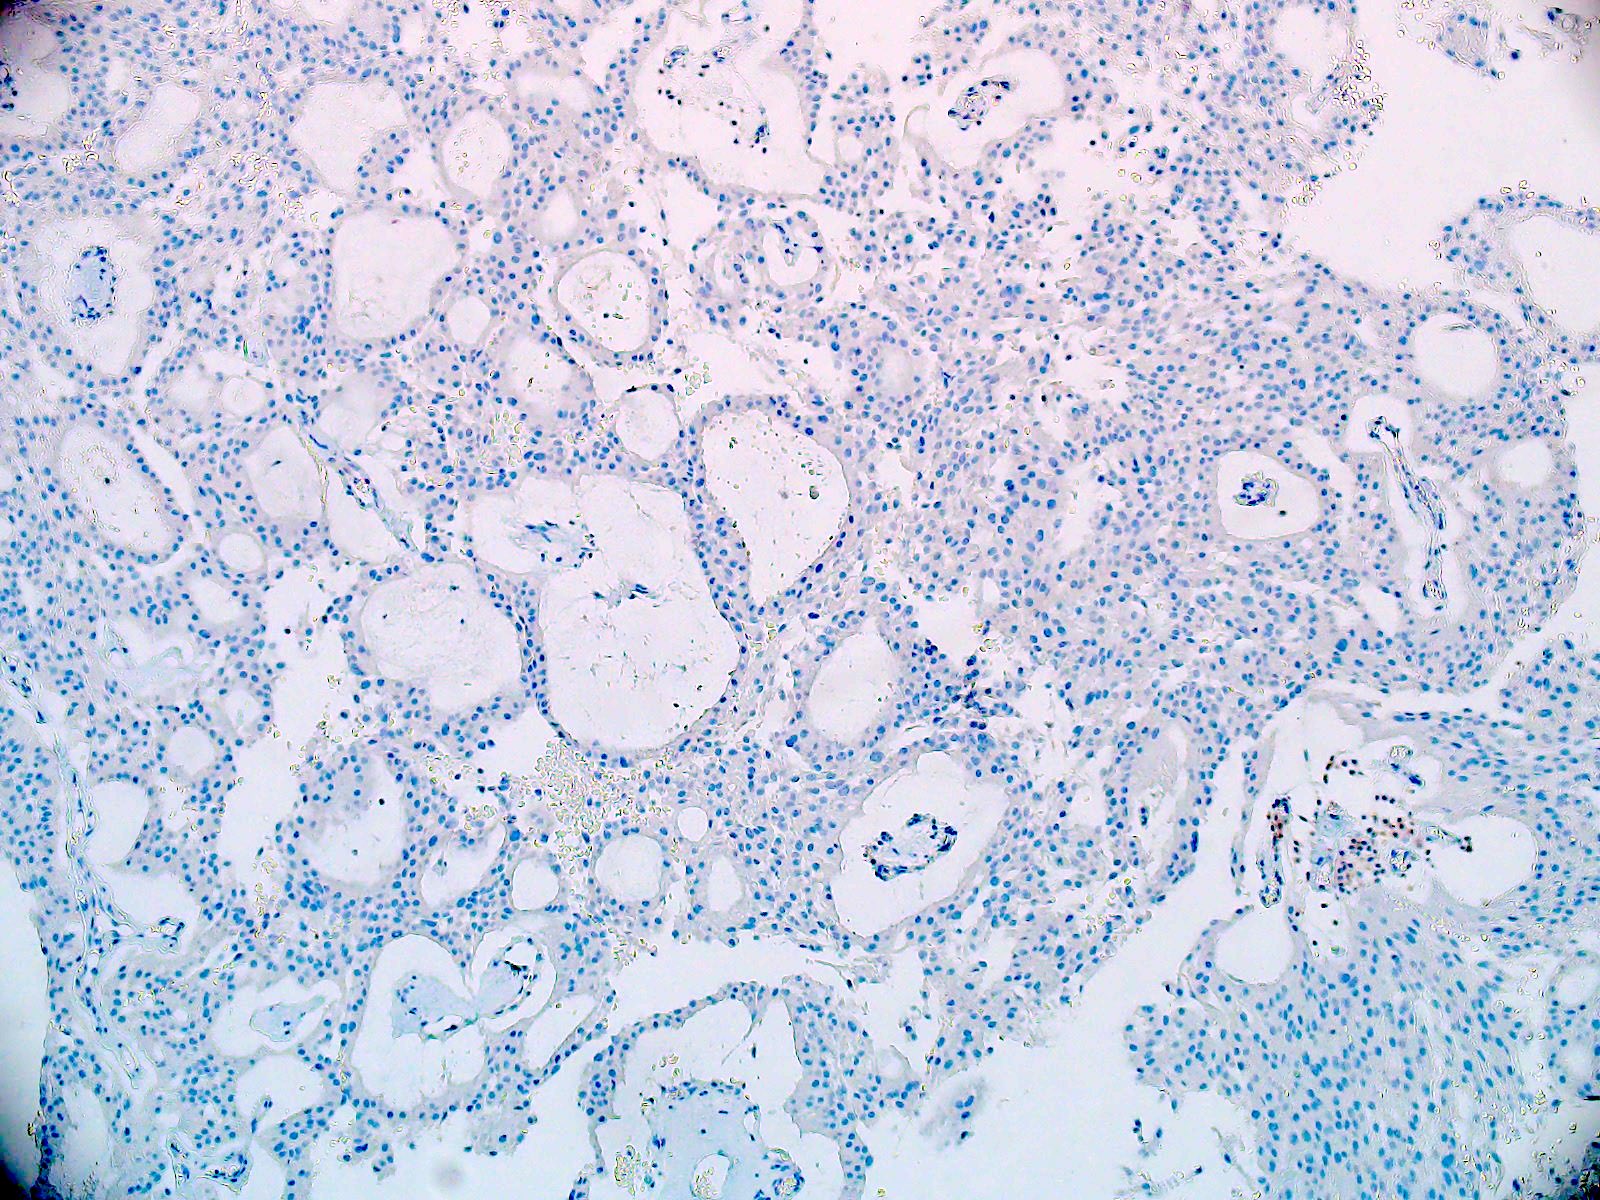

Microscopic (histologic) description

- Most common pattern is radial arrangement of cuboidal to epithelioid elongated glial tumor cells around hyalinized fibrovascular (central, often hyalinized blood vessels) cores in a papillary configuration

- Accumulation of basophilic myxoid material around blood vessels (myxoid stroma) and in microcysts

- Myxoid material is highlighted by PAS and Alcian blue positive staining

- In cases composed of confluent sheets of epithelioid cells with little or no papillary structures, PAS and Alcian blue positivity is useful in reaching a correct diagnosis

- Fascicular growth and spindle cells are common

- Pleomorphic tumor giant cells can be seen

- Occasionally tumor cells show distinctive eosinophilic balloons; these are PAS positive spherules that demonstrate spiculated reticulin staining (Am J Surg Pathol 1996;20:1091)

- Uncommon examples reported as anaplastic myxopapillary ependymomas show hypercellularity and reduced mucin in association with at least 2 of the following features: ≥ 5 mitoses / 10 high power field, Ki67 labeling index ≥ 10%, microvascular proliferation, spontaneous necrosis (Brain Pathol 2019;29:75)

Microscopic (histologic) images